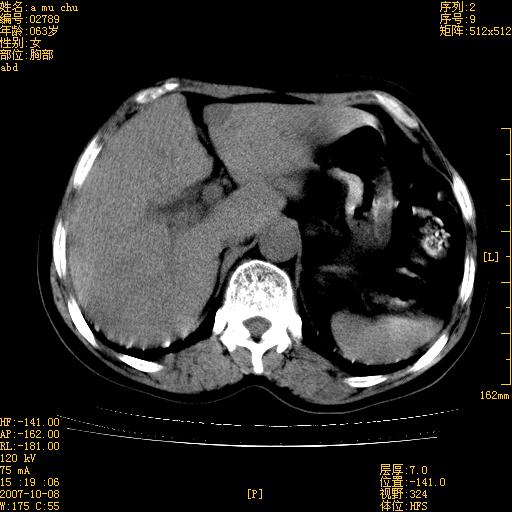

以下是引用王维浦在2007-10-17 21:02:00的发言:[br]胆囊增大,囊壁明显不规则增厚,邻近肝组织浸润,肝内外胆管无扩张。诊断:胆囊ca;[br]胰头软组织肿块影,考虑是由转移肿大的胰后淋巴结、没有肠道准备的十二指肠及胰头共同形成。[br]

以下是引用zhangzexing在2007-10-18 7:13:00的发言:[br]支持胰头占位,慢性胆囊炎. 2.肝左叶前外侧段占位,血管瘤?建议增强

以下是引用影像实习生在2007-10-17 19:49:00的发言:[br]支持胰头占位,慢性胆囊炎. 2.肝左叶前外侧段占位,血管瘤?建议增强.

以下是引用刘振江在2007-10-17 19:42:00的发言:[br]没有增强,胰头癌?胆囊及肝左叶占位?